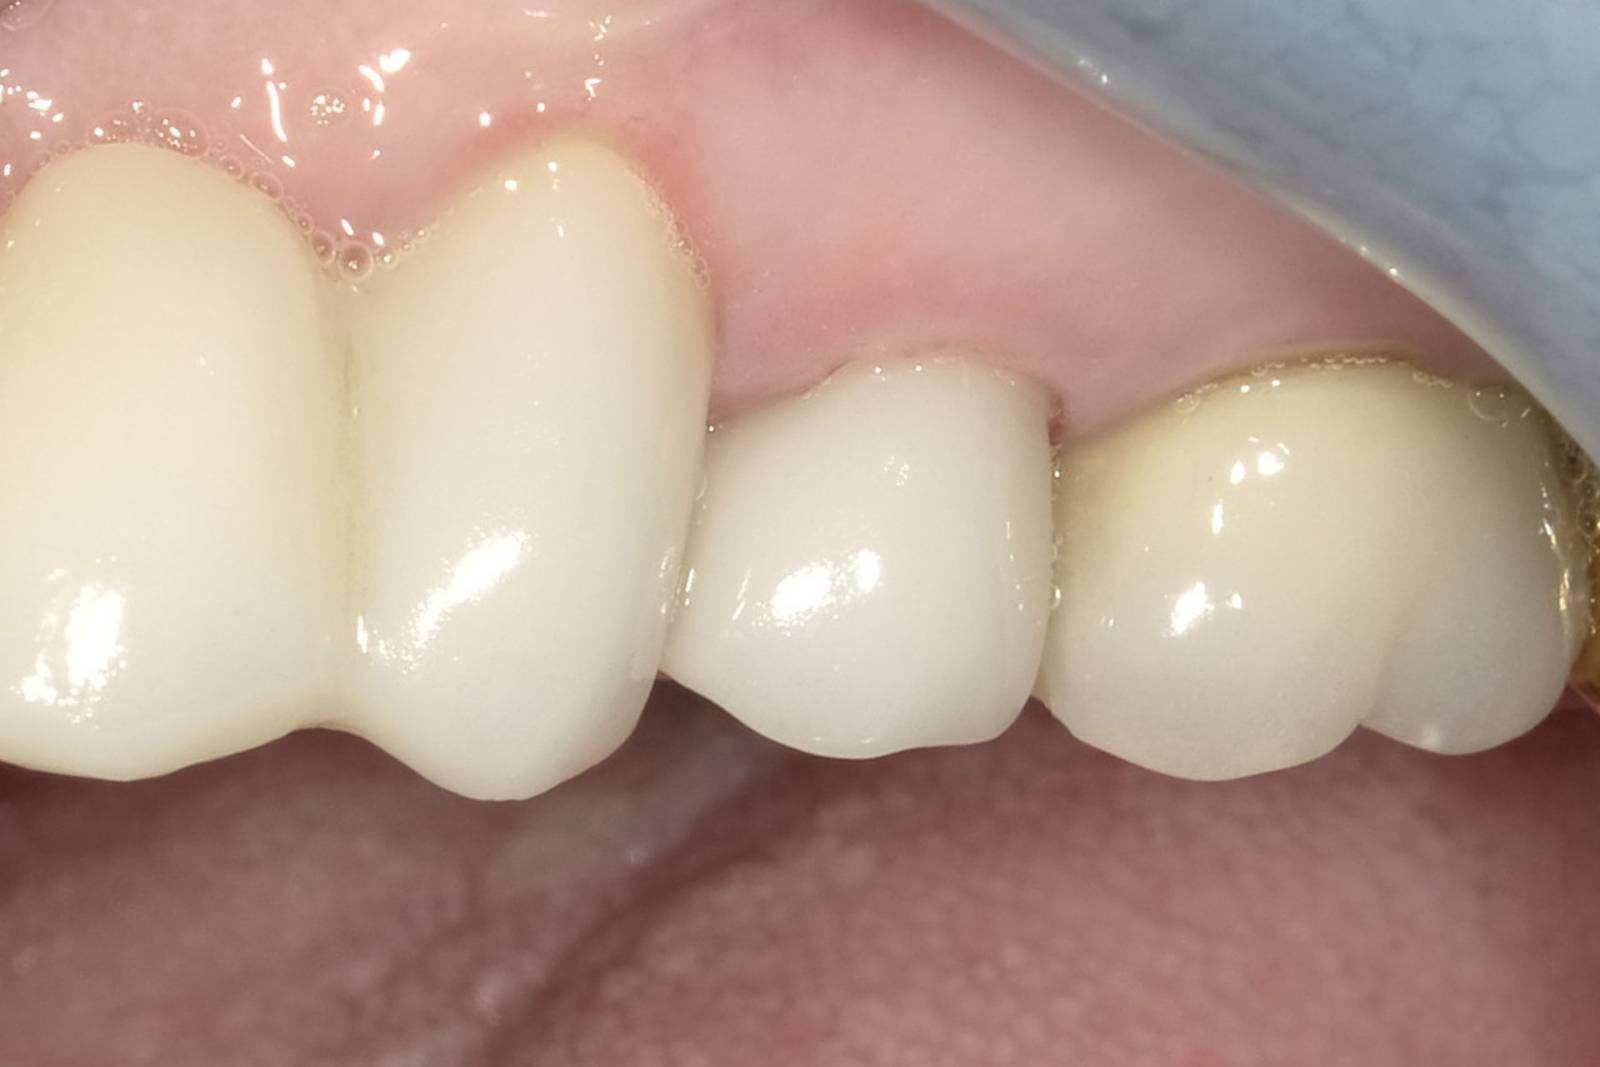

Second upper premolar

Astra Tech implant placement and an IPS e.max CAD single crown

A 36-year-old patient came to our practice four months after the extraction of tooth 15 to close the resulting tooth gap with an implant. Six months after the guided surgery, the patient presented with healthy gingiva and bone conditions.

Before: Absence of tooth 15 due to a longitudinal fracture. Patient wanted to close the resulting tooth gap.

After: A high-quality glass-ceramic crown providing a highly aesthetic and long-term stable restoration.

Dr. Andreas Bindl

Zurich, Switzerland